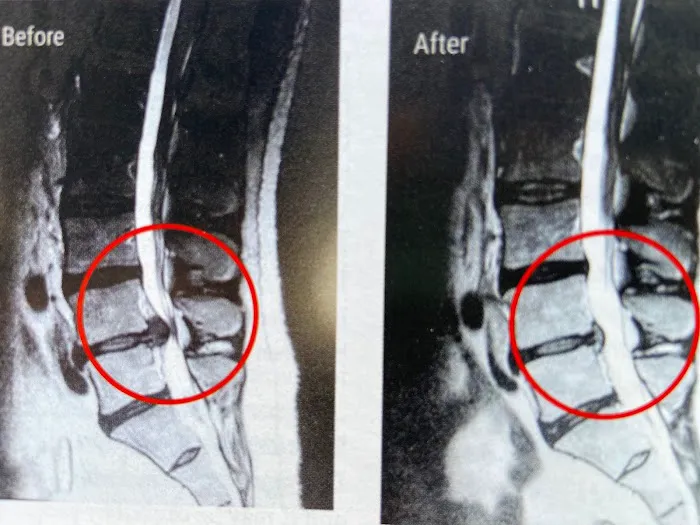

We specialize in non-surgical herniated disc treatment using the DRX9000 spinal decompression system, chiropractic care, and supportive therapies. Relieve back or neck pain, numbness, and sciatica at the source—without drugs, injections, or invasive procedures.